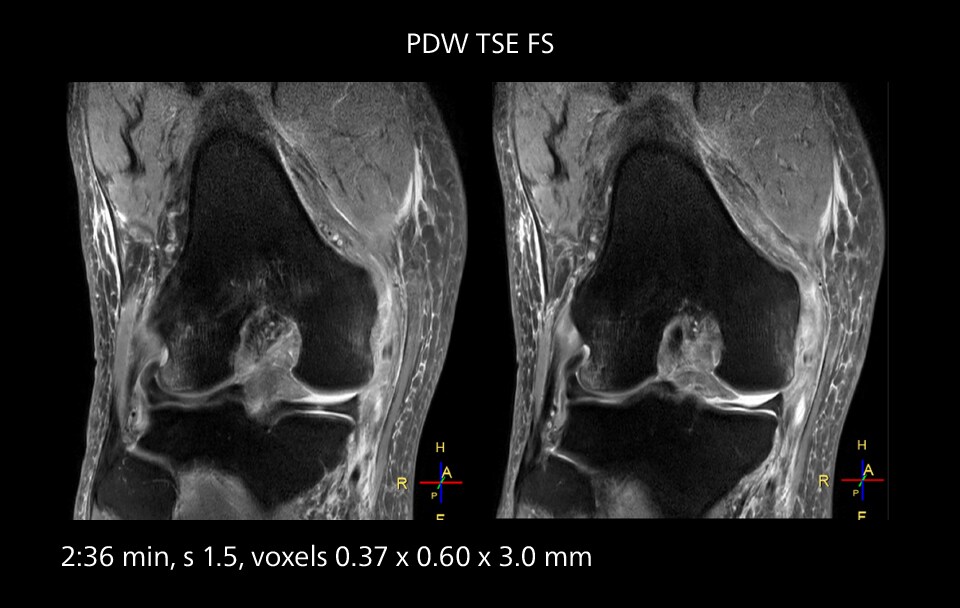

Images showing a posterior cruciate ligament (PCL) tear, a detached medial collateral ligament (MCL) on the tibial side and an intact anterior cruciate ligament (ACL). SmartPath to Elition X helped reduce scan time compared to previous imaging while maintaining resolution.

Sannodai Hospital radiologists had been very satisfied with their Ingenia 3.0T with Compressed SENSE, however after acquiring SmartPath to Elition X they have demonstrated improved image quality and even higher speeds in imaging studies throughout the body, according to Dr. Makuuchi.   “Generally, we were impressed by seeing that images are very sharp and have higher SNR than we used to get with our Ingenia 3.0T system,” he notes. “We were delighted to see that high image quality can be obtained in a short time thanks to the Elition with its powerful   An example of increased imaging speed is in knee studies. “There is a definite scan time reduction for T2* mFFE and proton density TSE – both of these sequences benefit from much shorter repetition times,” he reports.